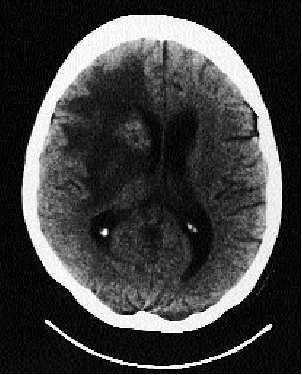

En la tomografía axial computarizada (TAC) craneal se observó una lesión ovoidea de 4 * 3 cm con componente hiper e hipodenso situada en el núcleo caudado derecho y otras de menos de 1 cm en el tálamo derecho; existe un importante edema frontoparietotemporal ipsilateral que produce una obliteración del asta frontal y del III ventrículo, comprimiendo parcialmente el cuerpo del ventrículo lateral derecho (fig. 1).

Fig. 1.